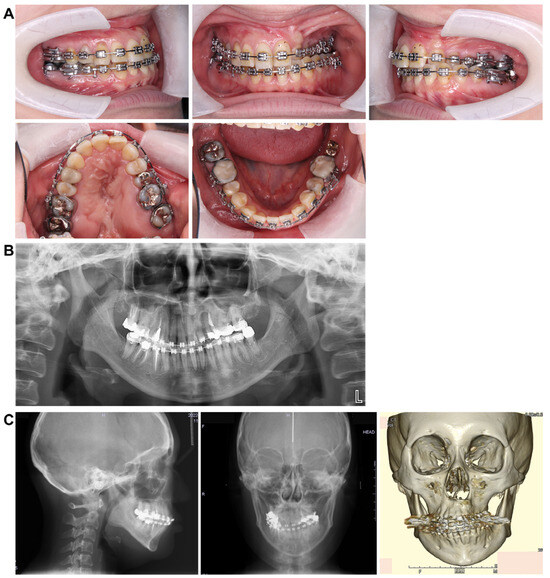

Figure 7.

Preoperative intraoral photograph and radiographs and CT. (A) Intraoral photographs. (B) Panoramic radiograph. (C) Cephalograms and CT.

3.3. Panoramic Cephalometric Radiograph (Figure 2A)

In the maxilla, the right first premolar, second molar, and left second premolar had undergone root canal treatment. Similarly, in the mandible, the right second premolar, first molar, and left second molar also underwent root canal treatment. An apical lesion was observed in the mandibular left second molar. Notably, wisdom teeth were present in the left maxillary and right mandibular regions. However, there was minimal curvature of the teeth roots, and the alveolar bone level appeared normal throughout the dentition.

3.4. Lateral and Frontal Cephalometric Radiographs (Figure 2B)

The SNA angle (evaluation of the anteroposterior position of the maxillary alveolar base relative to the skull base) was 73.0°, and the SNB angle (evaluation of the anteroposterior position of the mandibular alveolar base relative to the skull base) was 72.0°. The ANB angle (evaluation of the anteroposterior positional relationship of the upper and lower alveolar bases) was +1.0°, the skeletal system was skeletal 1, and the plane angle of the lower edge of the mandible was 35.0°, indicating a high mandibular plane. The U1 to FH (maxillary central incisor axis angle) measured 104.0°, while the L1 to Mand.P (mandibular central incisor axis angle) was 86.5°, showing a lingual inclination of the maxillary central incisor axis.

A standard frontal head radiograph revealed a 2.0 mm deviation of the facial midline, mandibular deviation, a cant tilted upward to the left by 4.0°, facial asymmetry, and deformation of both the maxilla and mandible.